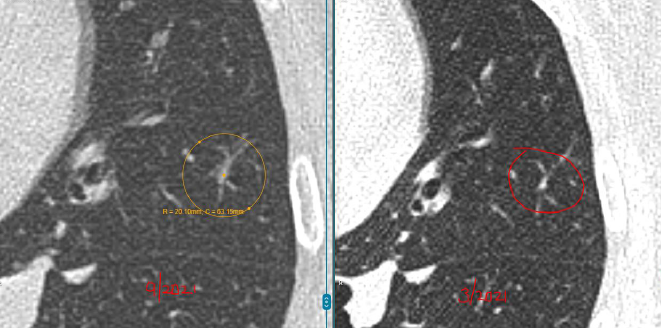

数年前,孙女士(化名)在一次体检中意外查出双肺多发结节:

左肺下叶:2枚实性结节,约5mm、3mm

右肺上叶:1枚磨玻璃结节,约4mm

每年复查,她都紧张得睡不着。好在3个结节都一直很“老实”,没变大。可四年后的一次CT复查,让她的心又提了起来:

左肺结节无变化,但右肺的4mm结节密度增高了,还又新添了一颗3mm的磨玻璃结节。

L教授详细查看了孙女士4年来的全部影像资料后,给出的结论让她长舒了一口气。

教授指出,右肺那颗4mm的磨玻璃结节虽然密度略有增加,但变化非常小,还不足以判断为恶化。

而左肺的两枚实性结节稳定了三年多,良性可能性超过99%。另外舌叶可见线状影,较前稳定,符合炎性、瘢痕特征。

至于新出现的那颗3mm磨玻璃结节,教授认为它也很“温和”,更像是一种暂时的炎性反应,有可能过段时间就自行消失了。

“这些结节都太小,目前还不到该切的程度,继续观察很安全。”L教授说。他建议孙女士每年复查一次CT,不需要手术、不用活检。